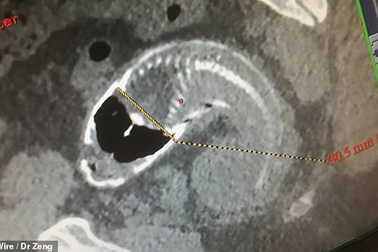

Kinh hoàng phát hiện “nguyên con cá rô phi trong bụng”Vây sắc nhọn của cá rô phi đã làm thủng ruột già của một người đàn ông Trung Quốc khiến phòng phẫu thuật bốc mùi hôi thối.